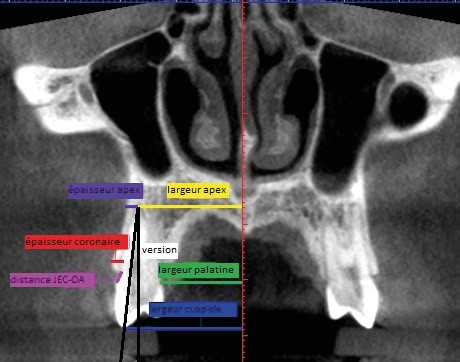

Sept mesures ont été réalisées pour quantifier le déplacement dentaire et les modifications alvéolaires (fig. 1 et 2). de chaque côté :

– largeur au niveau de l’apex ;

– largeur palatine mesurée au niveau du collet ;

– largeur au niveau de la cuspide vestibulaire ;

– quantité de version ;

– épaisseur de l’os alvéolaire à l’apex ;

– épaisseur de l’os alvéolaire coronaire mesurée à 2 mm apicalement à la crête ;

– distance jonction amélo-cémentaire-crête alvéolaire.